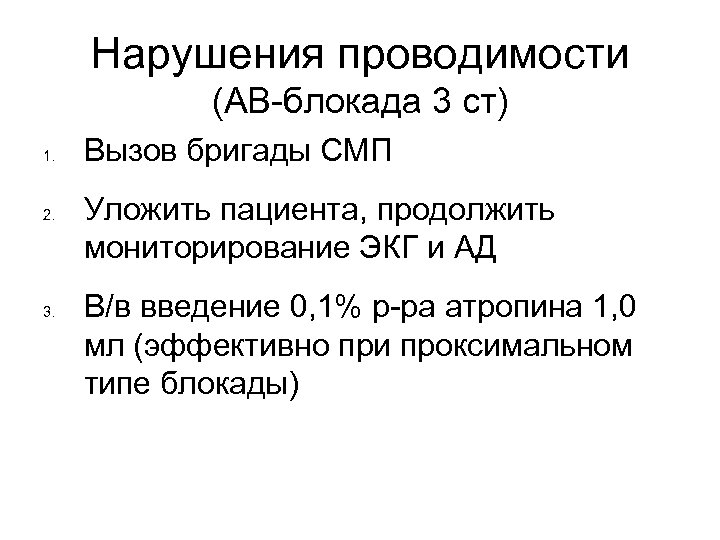

Нарушения проводимости (АВ-блокада 3 ст) 1. 2. 3. Вызов бригады СМП Уложить пациента, продолжить мониторирование ЭКГ и АД В/в введение 0, 1% р-ра атропина 1, 0 мл (эффективно при проксимальном типе блокады)

Нарушения проводимости (АВ-блокада 3 ст) 1. 2. 3. Вызов бригады СМП Уложить пациента, продолжить мониторирование ЭКГ и АД В/в введение 0, 1% р-ра атропина 1, 0 мл (эффективно при проксимальном типе блокады)